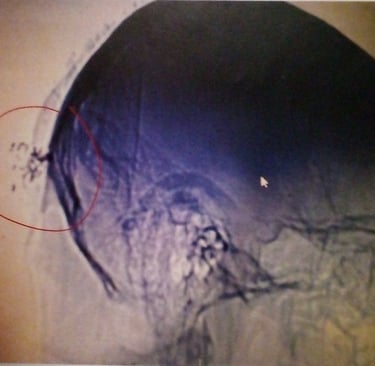

The most vulnerable area of the head:

The temple is where the frontal, parietal, temporal, and sphenoid bones meet, creating a weak point in the skull.

The middle meningeal artery, which supplies blood to the brain, lies directly under this thin bone. A strong blow can fracture the bone and rupture the artery, leading to blood collecting between the skull and brain (epidural hematoma), causing severe pressure and potential brain damage or death. Other vulnerable areas include the pterion, a thin spot just behind the temple, and the jaw, which can transmit force to the brainstem.

Targeted Individuals are attacked by beams of directed energy while sleeping that heats their brains and causes brain damage.